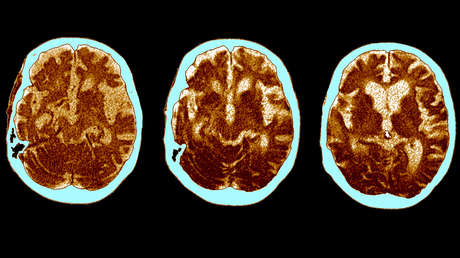

El impacto que tiene sobre la capacidad cognitiva haber sufrido un covid-19 grave es similar al que experimentamos los humanos entre los 50 y los 70 años y equivale a perder 10 puntos de coeficiente intelectual, se afirma en un comunicado emitido por un equipo de científicos de la Universidad de Cambridge y el Imperial College de Londres el 3 de mayo.

El estudio encontró que la extensión de estos deterioros cognitivos se correlacionó significativamente con la gravedad de la enfermedad de cada paciente. Los pacientes con covid grave que habían requerido ventiladores en el hospital experimentaron el deterioro cognitivo más significativo. La magnitud de la pérdida resultó similar a los efectos del envejecimiento humano entre los 50 y los 70 años, y equivalente a perder 10 puntos de coeficiente intelectual.

Los investigadores barajan varias causas de este deterioro cognitivo y suponen que lo más probable es que se trate de una combinación de factores que, además de una infección viral directa, podrían incluir "el suministro inadecuado de oxígeno o sangre al cerebro, el bloqueo de vasos sanguíneos grandes o pequeños debido a la coagulación y hemorragias microscópicas".